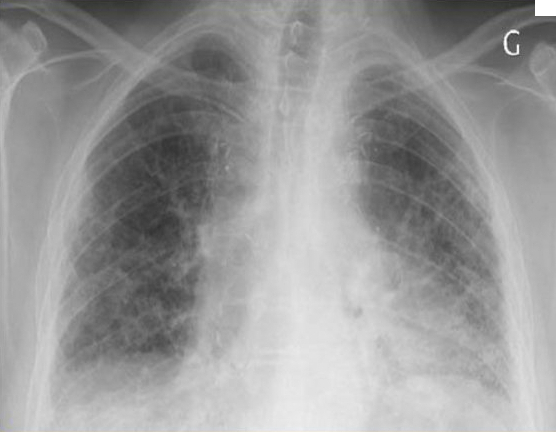

La radiographie de thorax est la suivante.

Figure 1.

Question 1 - Qu’est-il possible d’affirmer d’après la radiographie de thorax (une ou plusieurs réponses exactes) ?

Prédominance de réticulations de manière diffuse.

Culs de sac pleuraux bien visibles.

Absence de cœur en goutte, d’aplatissement des coupoles et d’horizontalisation des côtes.

Un syndrome interstitiel est évoqué sur la radiographie thoracique devant la présence de réticulations diffuses majoritairement. Ces traits sont orientés dans toutes les directions, pouvant dessiner ainsi des polygones correspondant aux lobules pulmonaires.

Le syndrome interstitiel radiologique peut être composé de :

– réticulations (« traits » correspondants aux septa lobulaires) ;

– micronodules (< 3 mm) ;

– épaississements péribronchovasculaires ;

– verre dépoli.